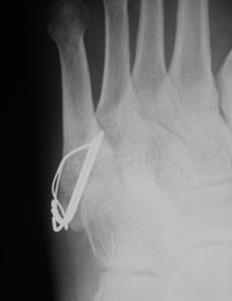

중족골은 발의 5개로 이루어진 뼈로 몇 번째 뼈가 골절되느냐에 따라 앞에 숫자가 붙습니다. 제5중족골은 새끼발가락 쪽 뼈에 해당합니다. 보행 중 바닥의 단차로 안쪽으로 발이 비틀렸을 때 자주 일어나며, 뼈의 어긋남이 없는 골절은 깁스로 고정하거나 압박붕대로 고정하는 등의 보존치료등을 시행하며, 어긋남의 편차가 크다면 강선과 와이어 등으로 고정하는 수술을 하게 될 가능성이 있습니다.